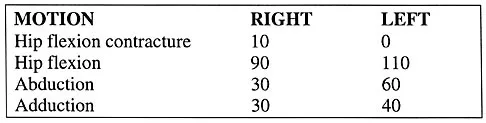

A 14-year-old football player has had thigh pain and weakness following a full-contact scrimmage 24 hours ago. He recalls that he felt a sharp pain in his back after colliding with a much heavier player. Examination reveals that the spine is minimally tender to palpation in the upper lumbar region. Motor testing reveals quadriceps weakness bilaterally, and a reverse straight leg raising test is positive. Plain radiographs of the thoracolumbar spine are normal. A myelogram, a CT scan with contrast, and an MRI scan are shown in Figures 41a through 41c. What is the most likely diagnosis?